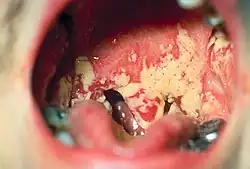

Die Mundschleimhaut ist gerötet und entzündlich verändert – die klassischen Entzündungszeichen sind sichtbar. Weitere Symptome sind Mundgeruch, Appetitlosigkeit bis hin zur kompletten Ess- und Trinkverweigerung (bei Kleinkindern), vermehrter Speichelfluss (Hypersalivation) sowie leicht auszulösende Mundschleimhautblutung (z. B. durch eine harte Zahnbürste).